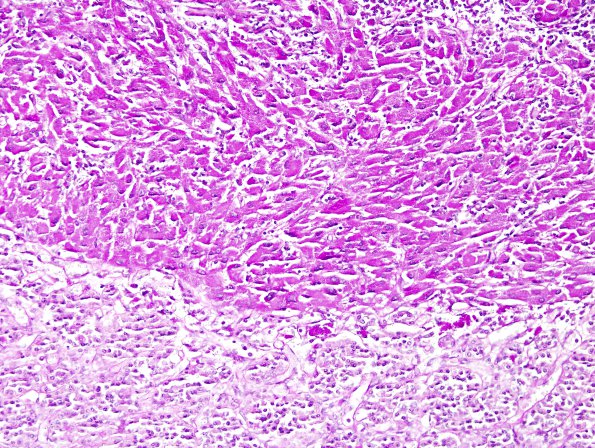

TTF-1-positive sellar tumor - Granular cell Tumor

1E2 Granular Cell Tumor (Case 1) PAS 2A

1E2,3 Higher magnification of PAS+ reactive GCT tumor cells (PAS, no diastase)